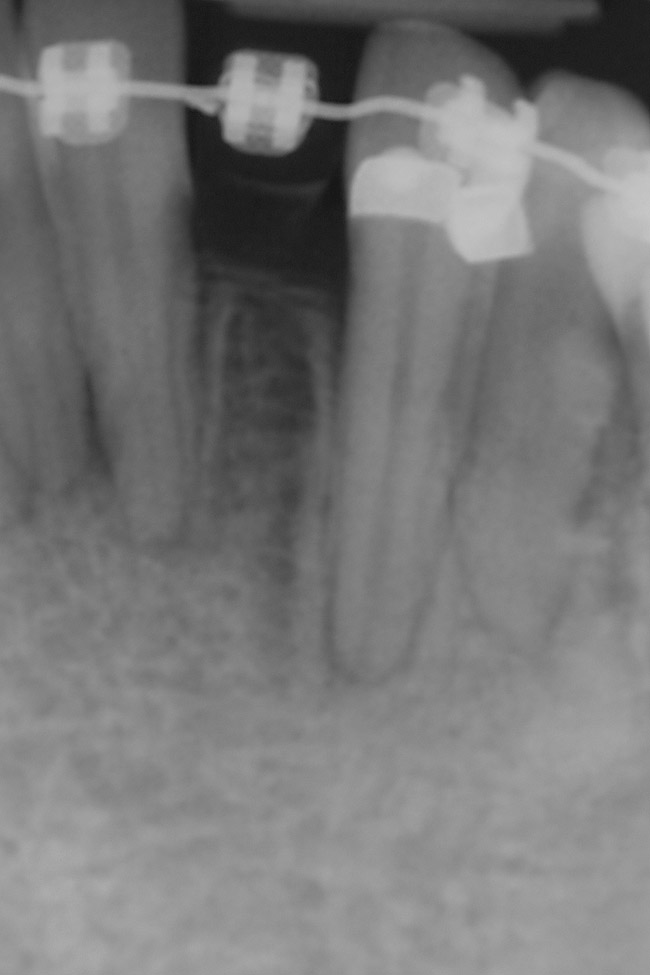

Figure 10  Radiograph of orthodontic distraction osteogenesis.

Figure 10

Figure 11  Radiograph showing developed implant site of tooth No. 23.

Figure 11

This treatment plan was elected with the premise to reevaluate treatment options during orthodontic tooth movement. Soft-tissue augmentation was initiated to correct the mucogingival defect in the area of teeth Nos. 21 and 22. A free gingival graft was performed to achieve an adequate band of attached and keratinized gingiva to resist potential stripping on the root surfaces of teeth Nos. 22 and 21 during orthodontic movement (Figure 8). Orthodontic movement then was initiated to site-develop position No. 23 for an implant (Figure 9 through Figure 11). Orthodontics also was used to idealize the patient’s occlusion and develop canine guidance to minimize occlusal load and maximize the redistribution of forces36-40 for protecting the future implant from deleterious forces. The space was opened around the peg lateral tooth No. 7, and the gingival levels were aligned for maxillary incisors. Bonding was performed to restore the length of teeth Nos. 8 through 10 and to bond the peg lateral to a normal tooth form, which allows the orthodontist to idealize the posterior occlusal scene and maintain canine guidance (Figure 12 through Figure 13).

Following the first goal of orthodontia—moving tooth No. 22 to a proper functional and anatomical position—a periodontal reevaluation was performed, demonstrating an improvement in short- and long-term tooth prognosis. At this time, the decision was made to abort continual extrusion of teeth Nos. 21 and 22, although some attachment level discrepancy remained between Nos. 21 and 22 (Figure 14). Implant diagnostics ensued and included mounted study models and a diagnostic wax-up. A scanning appliance was created to demonstrate the desired prosthetic outcome requirements, and the patient was referred for computed tomography (CT) scans. CT scan assessment demonstrated successful orthodontically directed GBR to allow implant placement (Figure 15 through Figure 16). Only minor GBR therapy would be needed and could be accomplished simultaneously with implant installation. Guided implant placement occurred, using an open flap approach (Figure 17). During surgery, root dehiscences were noted on teeth Nos. 21, 22, 24, and 25, as well as the anticipated dehiscence following implant placement at No. 23 (Figure 18). A positioning reference (index) was secured after implant placement to facilitate a provisional prosthesis at stage II surgery. Cortical perforations then were placed adjacent to the implant to encourage angiogenesis (Figure 18), and mineralized freeze-dried bone allograft enhanced with platelet-derived growth factor was placed over the dehiscences for purposes of guided tissue regeneration and GBR (Figure 19). A highly resorbable collagen membrane was placed to stabilize the allograft. The flap was coronally repositioned, and primary-intention wound healing was achieved (Figure 20 and Figure 21). Following 4 months of stage I surgery, implant uncovery and immediate provisionalization were performed in conjunction with connective tissue grafting. Final orthodontic tooth movement then ensued, using the implant as anchorage to optimize end-tooth movements, interroot separation, and the cuspid-protected occlusal scheme. A final impression then was secured, and a zirconia abutment (Figure 22) with an all-ceramic restoration was fabricated for the prosthetic phase completion of No. 23 (Figure 23 through Figure 25).